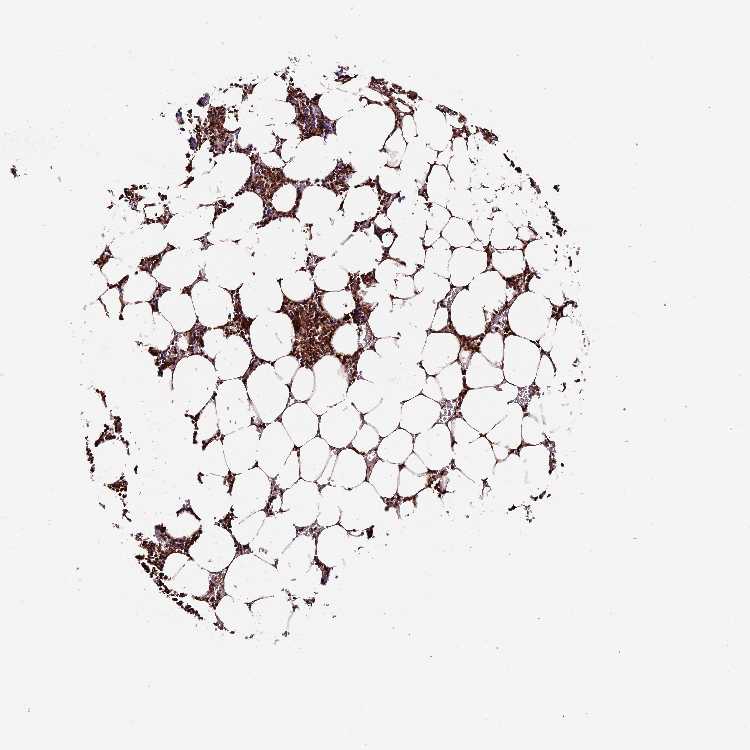

BONE MARROW - Antibody stainingi

Antibody staining in the annotated cell types in the current human tissue is reported as not detected, low, medium, or high, based on conventional immunohistochemistry profiling in selected tissues. This score is based on the combination of the staining intensity and fraction of stained cells.

Each image is clickable and will lead to virtual microscopy that enables deeper exploration of all samples and also displays staining intensity scores, fraction scores and subcellular localization as well as patient and tissue information for each sample.

Antibody HPA040390Antibody CAB002611

Hematopoietic cells HighNot detected